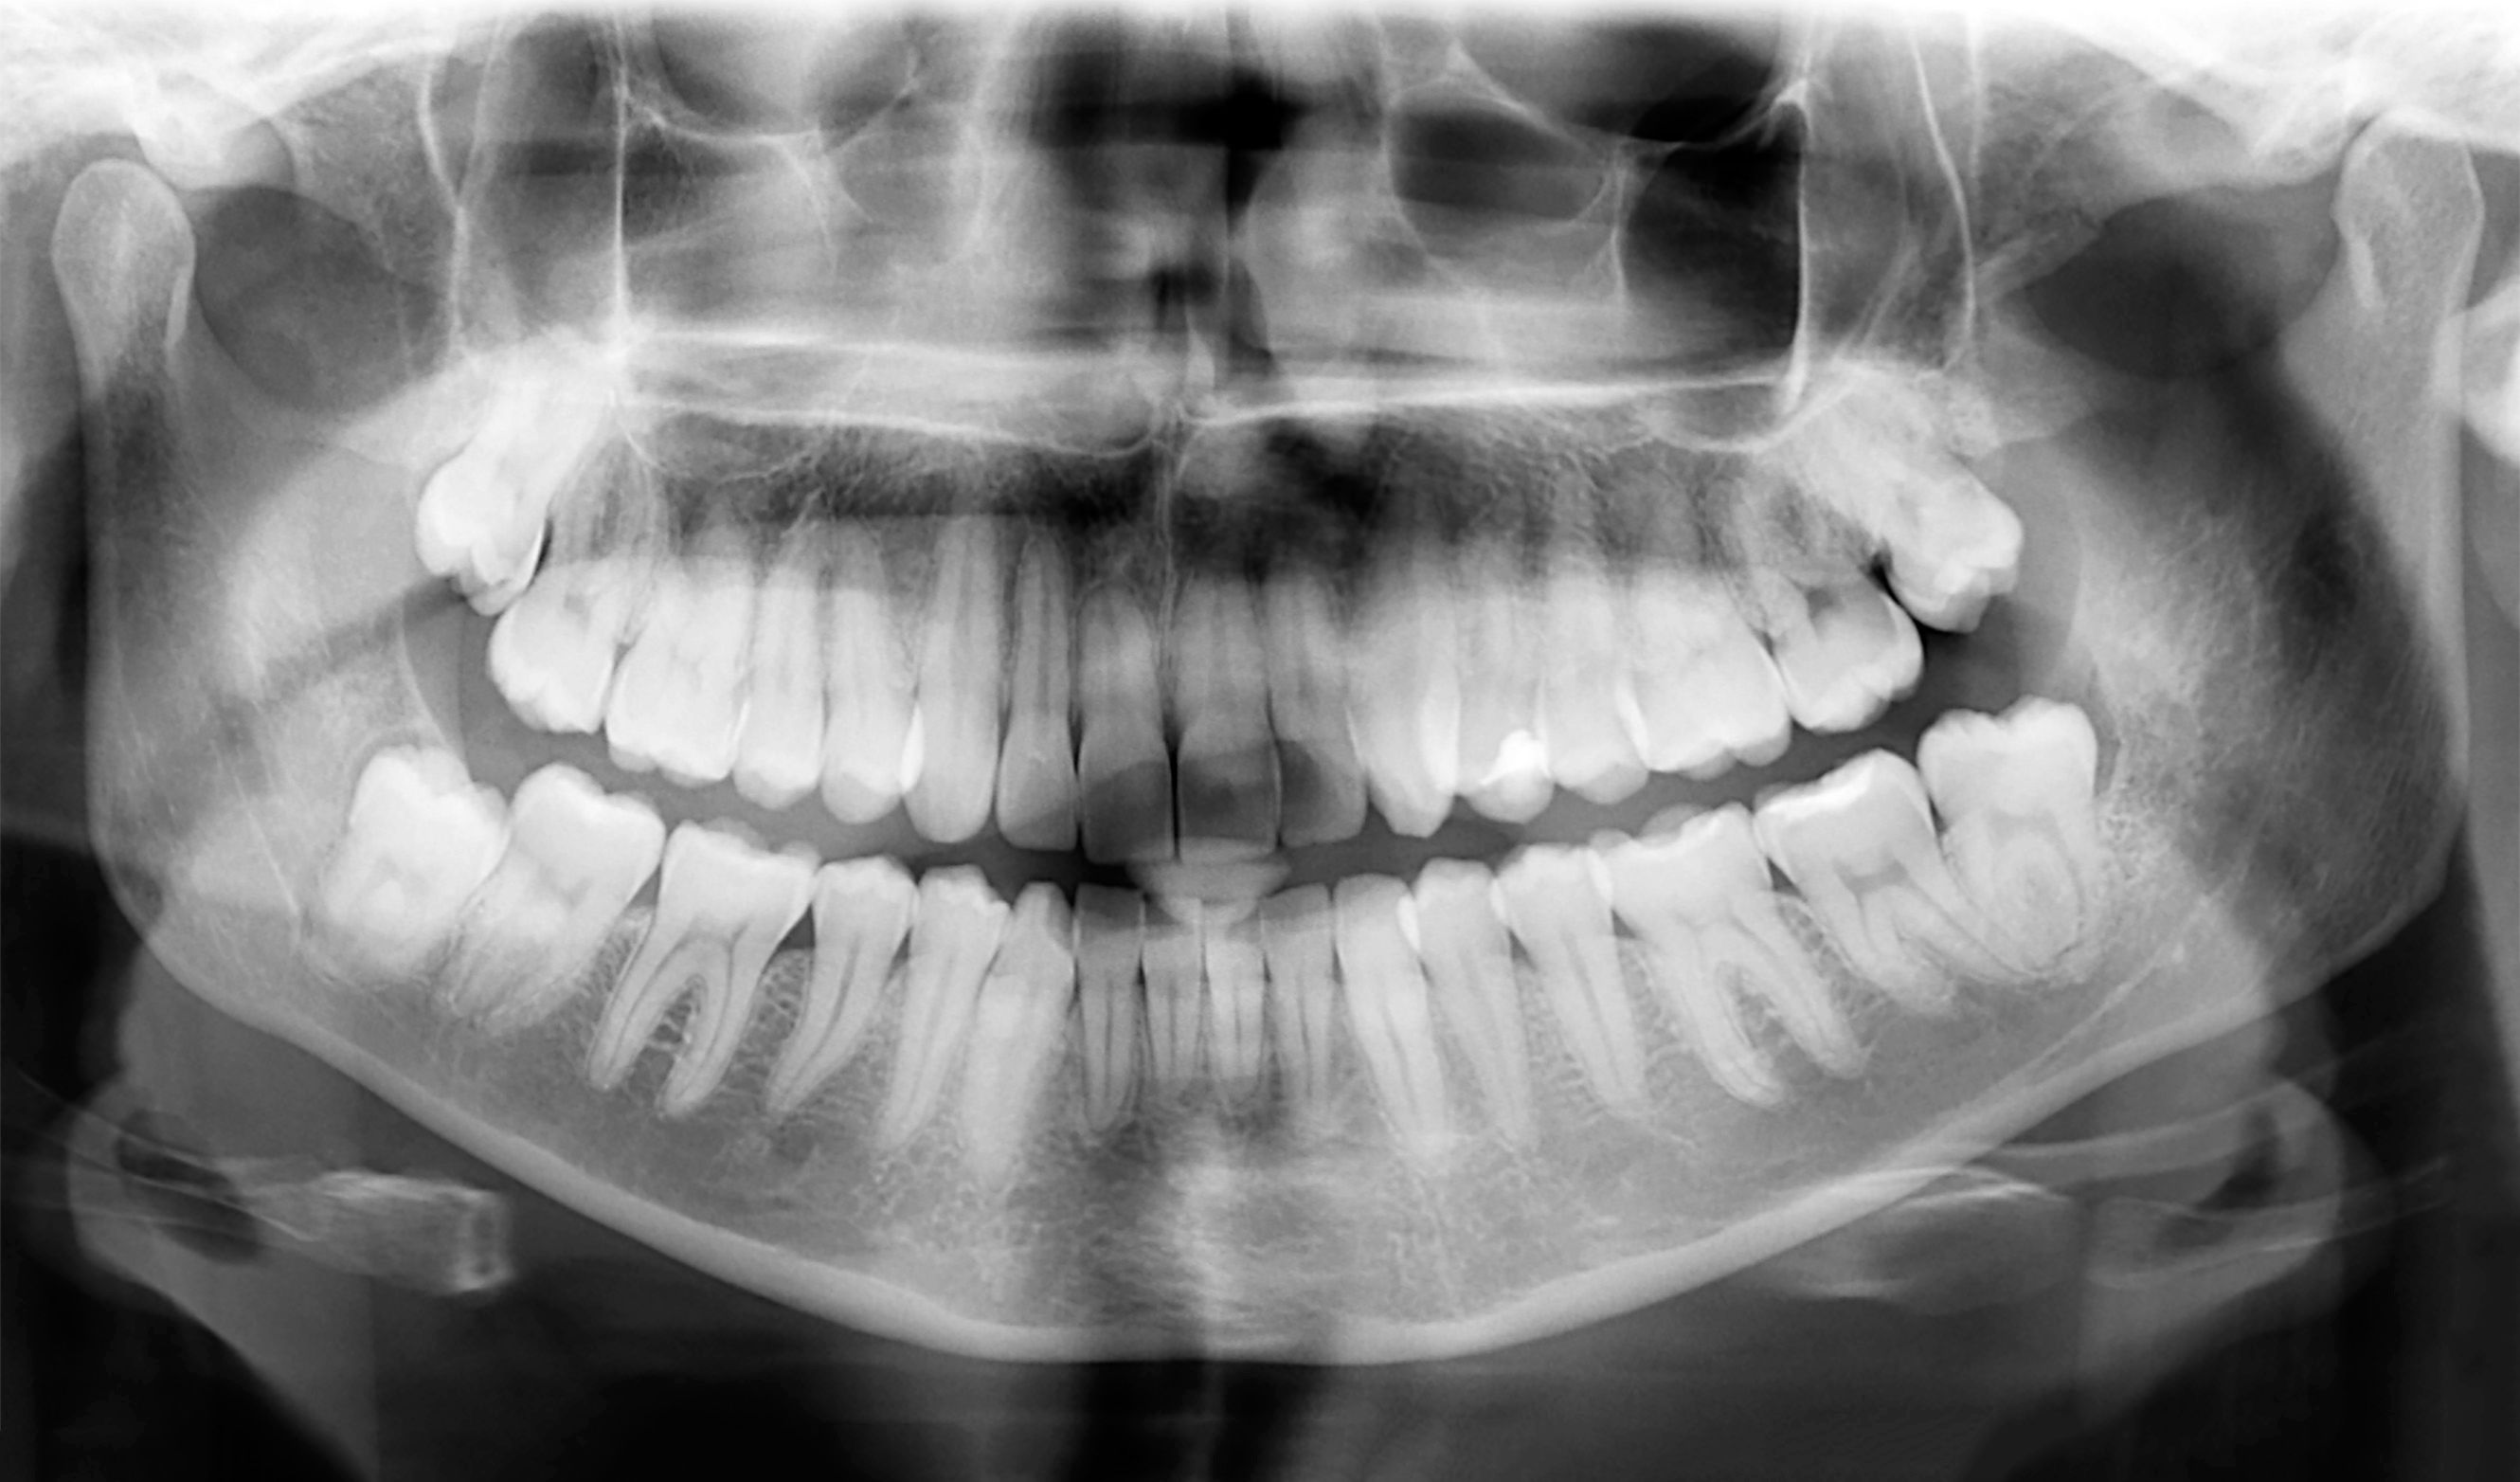

Panoramic X-Rays

Panoramic X-rays capture the entire mouth in a single image, making them ideal for evaluating wisdom teeth, jaw disorders, and planning orthodontic treatments. These are particularly useful in comprehensive diagnostic procedures.